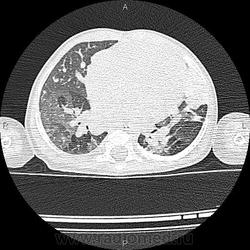

Основной диагноз ВПС: множественные ДМЖП (по типу "Швейцарский сыр"), ДМПП, состояние после оперативного лечения по поводу стеноза легочного ствола. В анамнезе - полисегментарная двустороняя пневмония, сейчас беспокоит кашель. Вопросы возникли по поводу участка уплотнения (V образование? зона консолидации? или еще что-то?) в язычковых сегментах в левом легком.

Обратитесь приватно к Ola-la, а мы почитаем. Не вполне копегаген, но какая-то мозаичная перфузия, ощущение "воздушных ловушек" при бронхиальной обструкции.